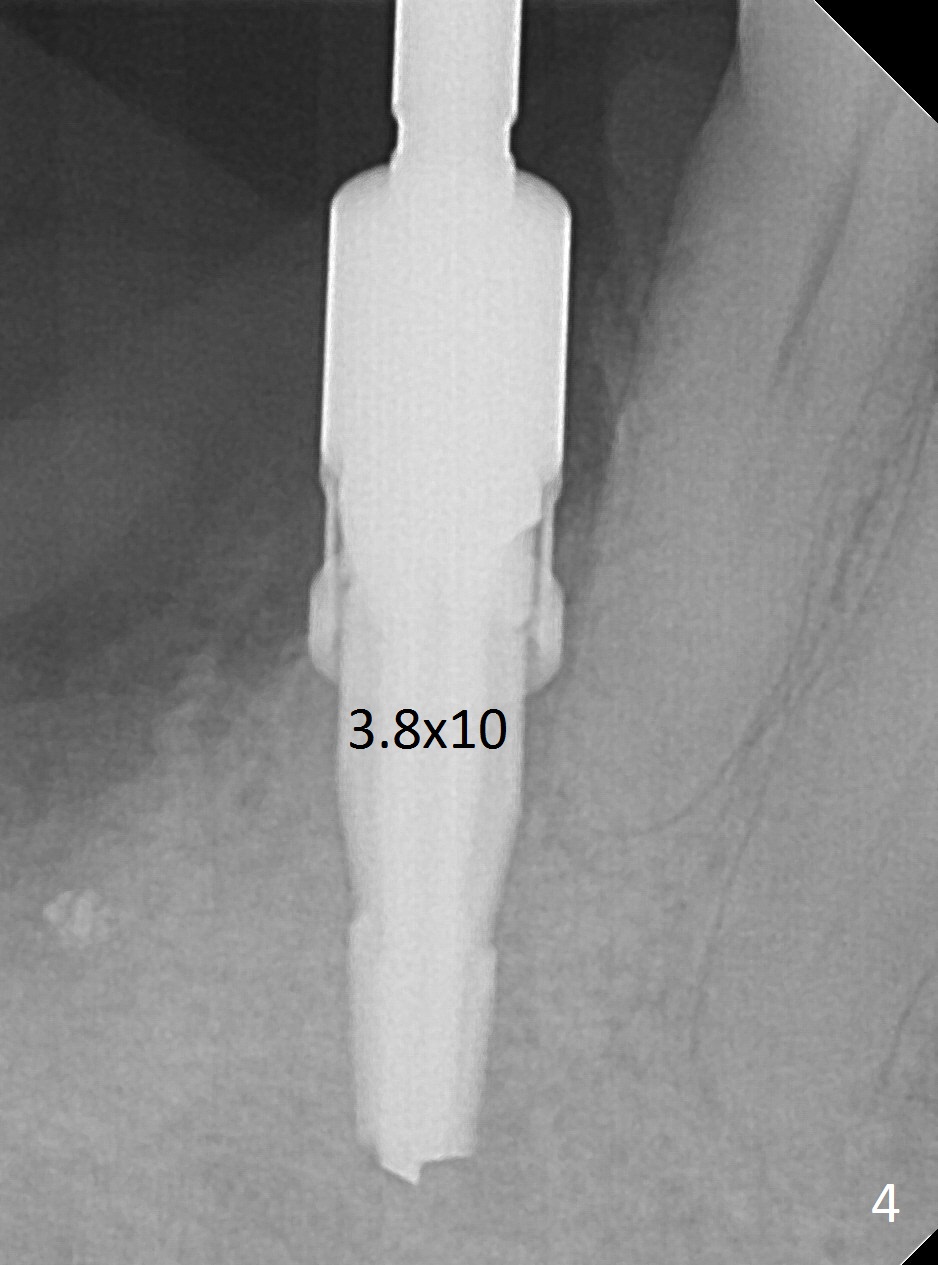

Initial osteotomy at #29-30 shows that there is clearance at #31, but not at #30 (Fig.1 (red dashed line: the superior border of the Inferior Alveolar Canal)) and that the osteotomy at #29 is close to the root of #28 (Fig.2). Moving the osteotomy of #29 distally using Lindamann bur is not sufficient (Fig.4 when a 3.8x10 mm drill is in place). A de novo osteotomy is established distally (Fig.5,6 (red dashed line: old osteotomy)).